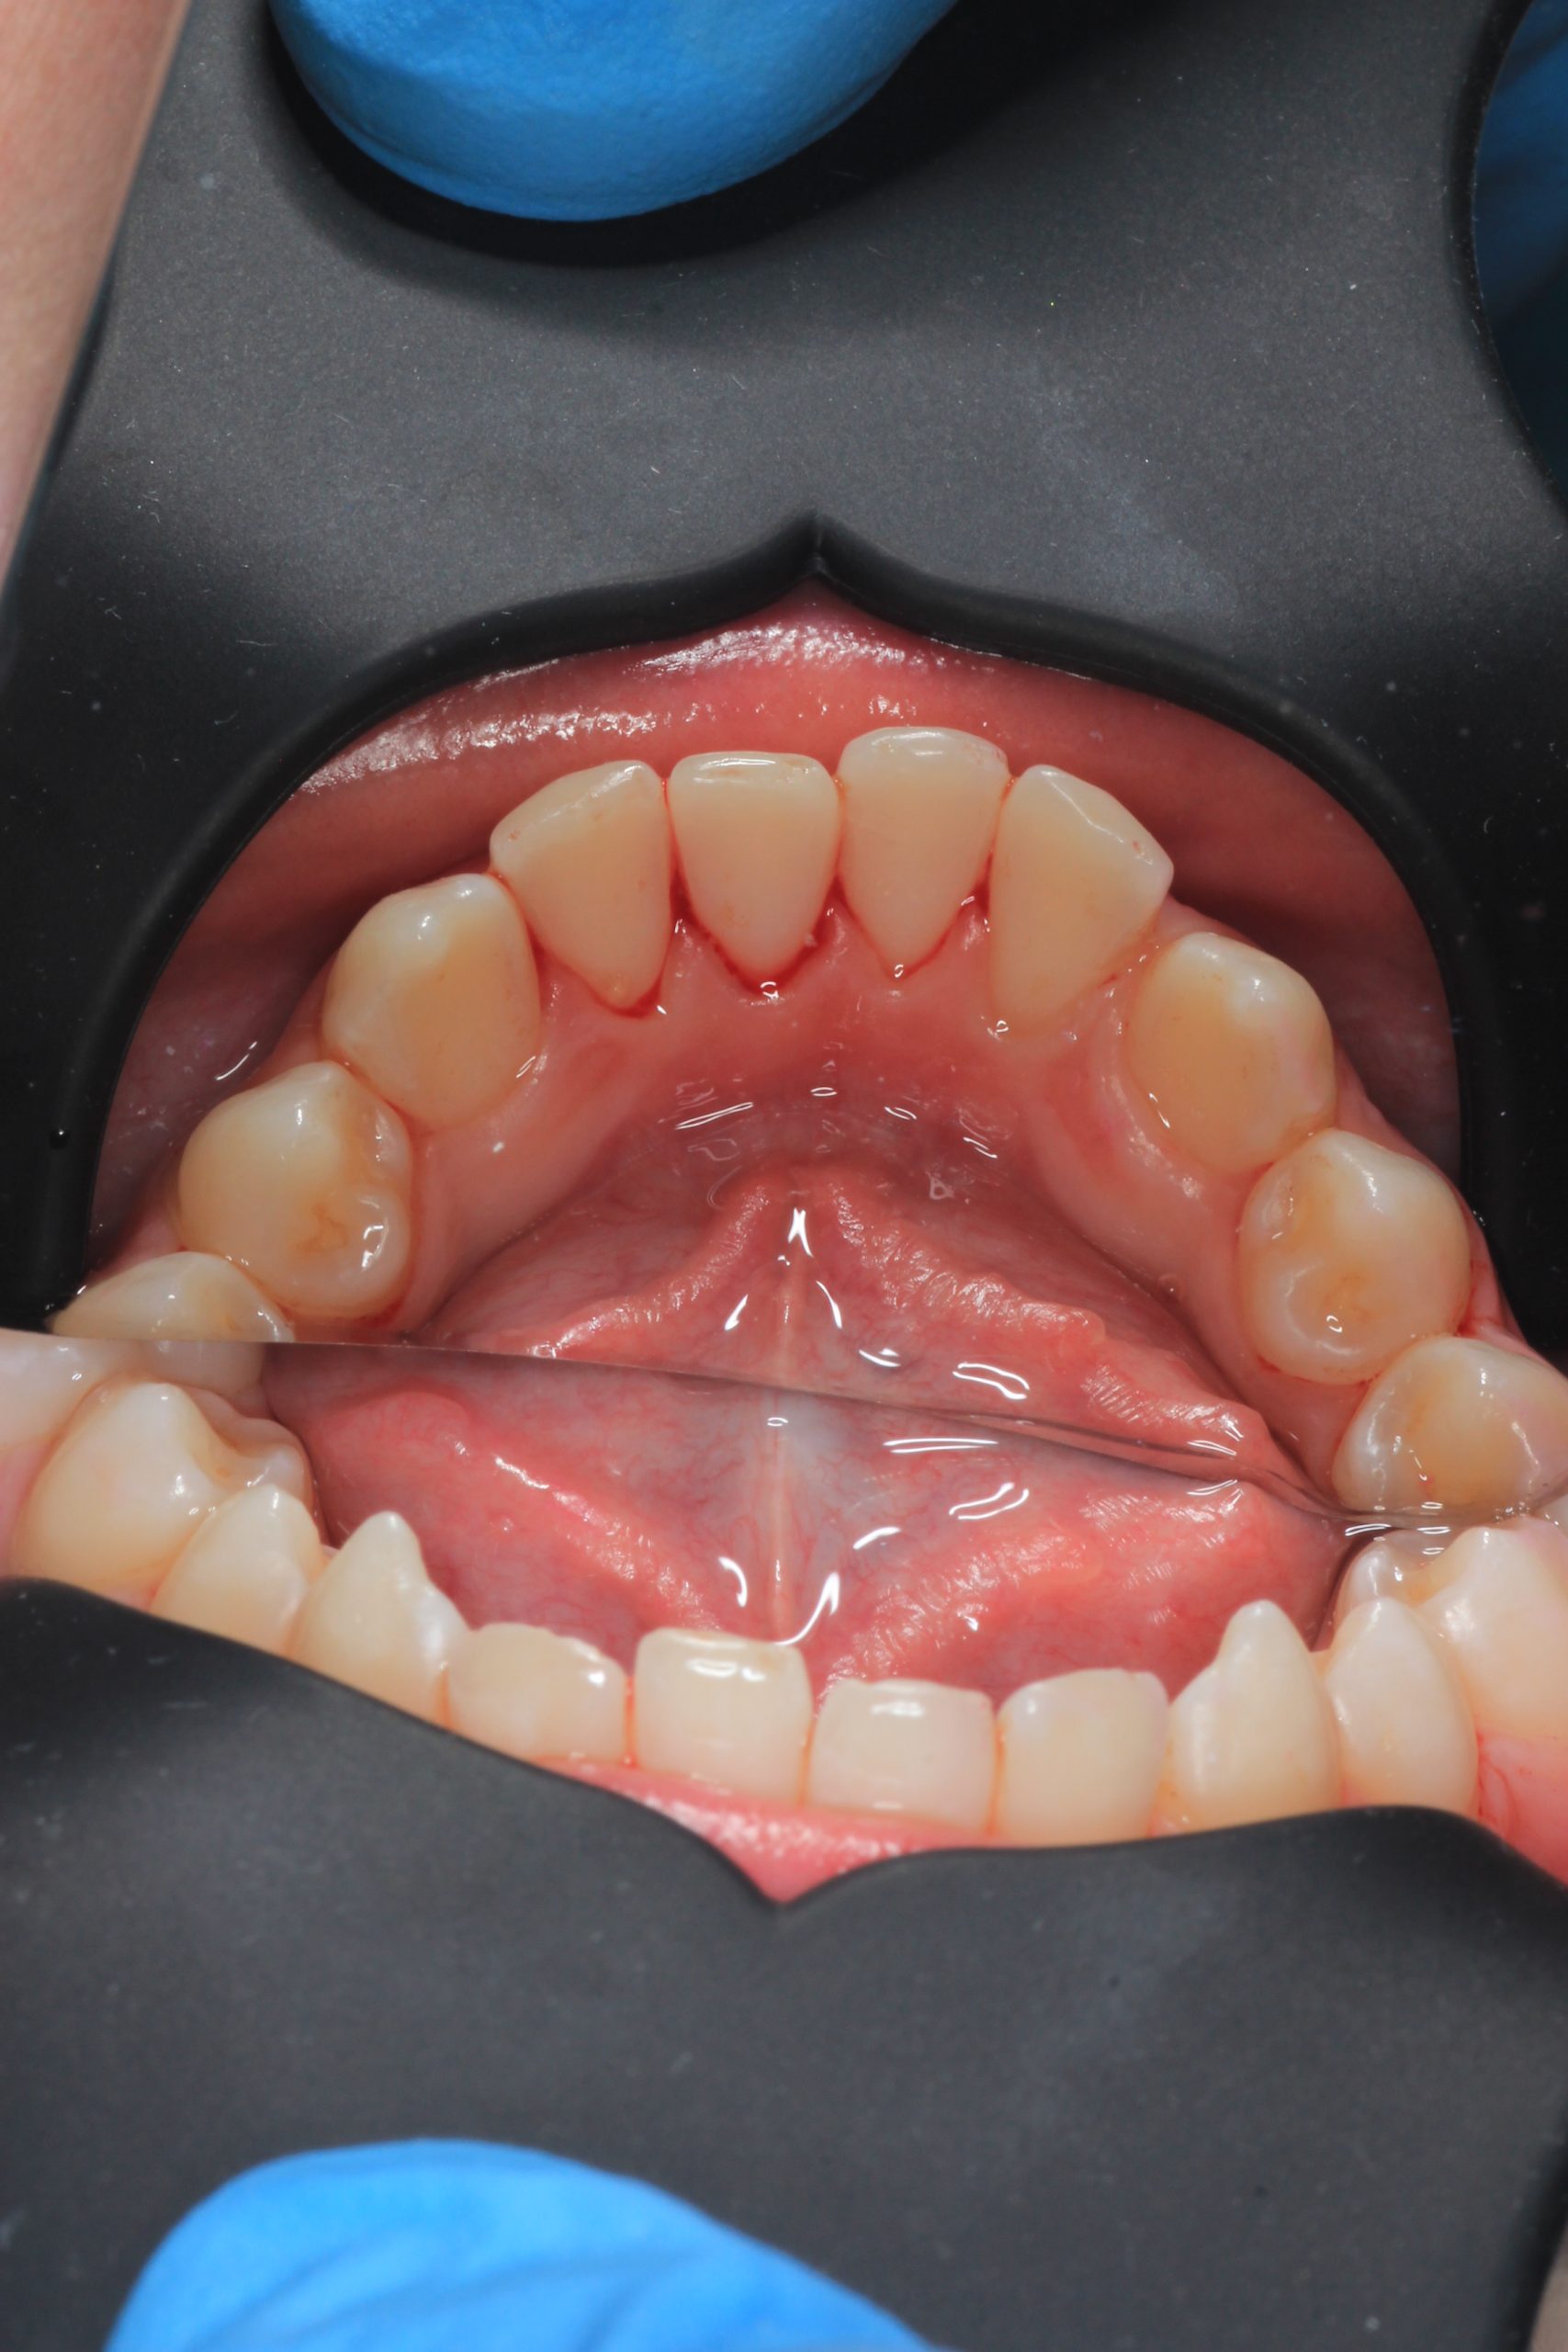

We examine the condition of teeth, gums, and bite. - Plaque Disclosure with Special Indicators

Areas that weren’t cleaned well appear purple. The darker the shade, the older the plaque. This helps both kids and parents understand where brushing needs to improve. - Brushing Training & Home Care Tools Selection

Together with your child, we practice brushing techniques, correct mistakes, and provide personalized recommendations. We advise whether to use manual or electric brushes, floss, interdental brushes, or remineralizing gels. - Plaque Removal with AIRFLOW Prophylaxis Master (EMS, Switzerland)